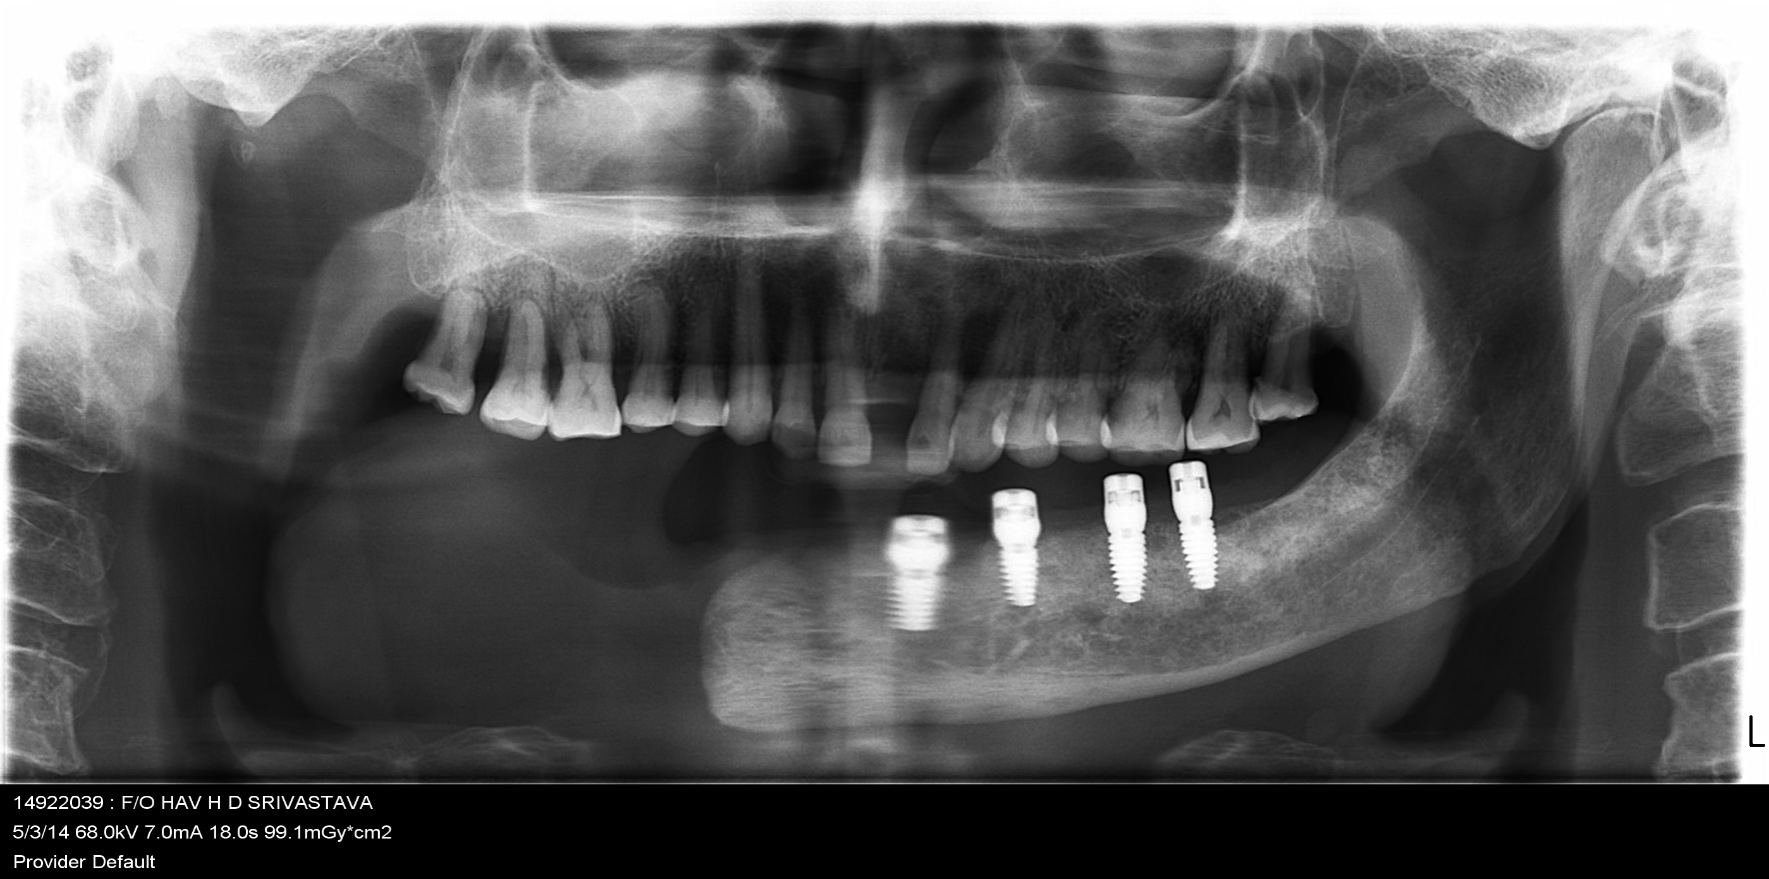

Strategic placement of 4 Dio dental implants in the regions 32, 33, 35, and 36 using advanced surgical techniques suitable for post-cancer reconstructed anatomy.

Implants were delayed loaded after 3 months with PFM crowns. Precision-attached metal removable denture was inserted for comprehensive hemimandibulectomy rehabilitation.

A 72-year-old male oral cancer survivor visited our dental center after surgical removal of the right side of his mandible. Patient had multiple missing and attrited teeth with significant functional impairment. Treatment involved implant-supported lower teeth with PFM crowns and precision-attached removable denture for hemimandibulectomy rehabilitation.